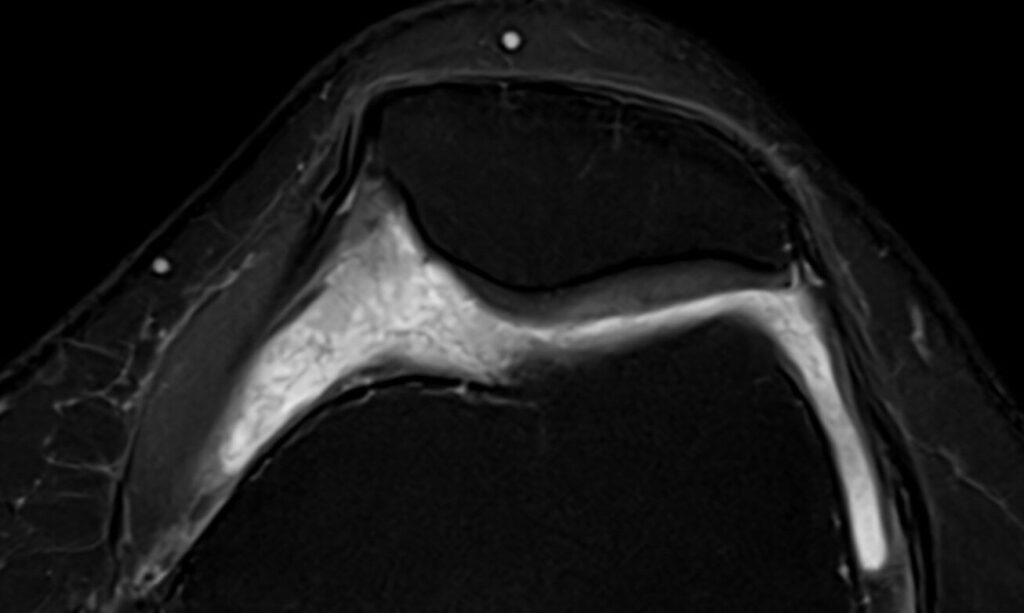

Morphologisch typisch sind filamentäre, bandförmige oder netzartige intraartikuläre Strukturen, die sich zwischen den Gelenkflächen, im suprapatellaren Rezessus oder im Hoffa-Fettkörper ausbreiten. Diese Veränderungen entsprechen fibrotischem Gewebe und zeigen im MRI ein low- bis intermediäres Signal in allen Sequenzen.

Im passenden klinischen Kontext gilt eine netzartige intraartikuläre Fibrose als nahezu pathognomonisch für eine Arthrofibrose. Die systematische Beurteilung dieser Strukturen ist daher entscheidend für die radiologische Diagnose.